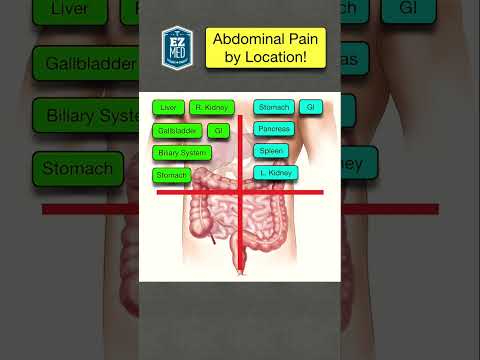

Abdominal Pain Differential Diagnosis

This video highlights different causes of abdominal pain according to the site of the pain in the abdomen. This is the first in a series of #shorts describing different causes of abdominal pain. DISCLAIMER: This or associated videos are not meant for self-diagnosis or a means of avoiding qualified medical care. Strictly for information only.

Abdominal Pain Causes by Location and Quadrant [Differential Diagnosis Chart]

🔥 Causes of Abdominal Pain in 60 SECONDS! [Differential Diagnosis by Location & Quadrant]